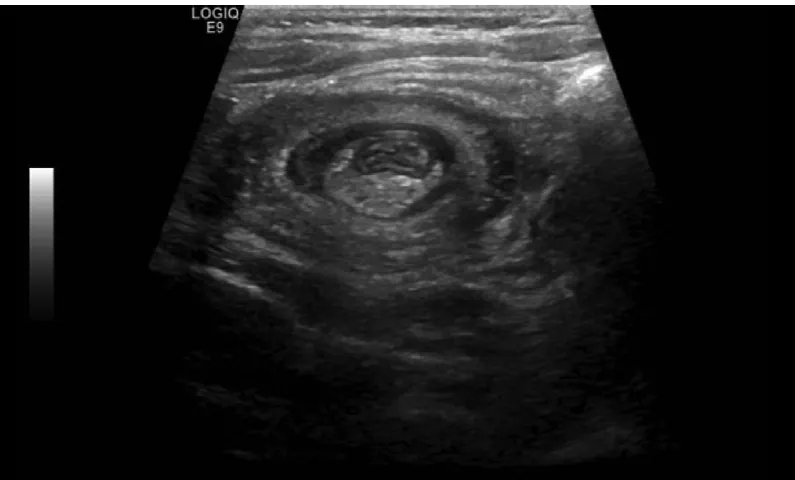

E2. 초음파

: 1st 검사 for 장중첩 진단 (정확도 : 거의 100%)

(1) 타겟사인(Target sign): 횡단면에서 동심원 모양

(2) 가성신장사인(Pseudokidney sign): 종단면에서 신장처럼 보임

초음파는 진단에 가장 적합한 영상 검사법이며, 타겟 사인(target sign) 또는 **가성신장 사인(pseudokidney sign)**을 평가할 수 있습니다.